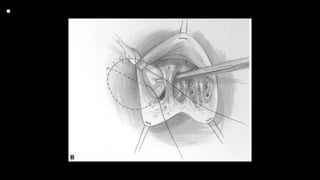

Exposure of ventricular septal defect

and right ventricular outflow tract

through tricuspid valve. B:

Infundibular resection is complete

and pulmonic valve can be seen.